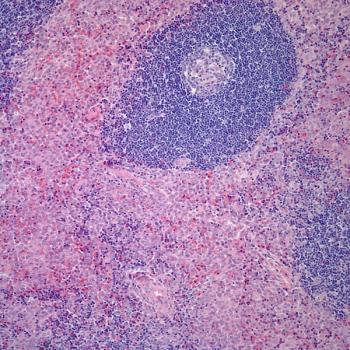

A 43-year-old man presents with a cough and chest pain. Imaging shows a mass in the lower lobe of his right lung, and a biopsy is performed. What is your diagnosis?